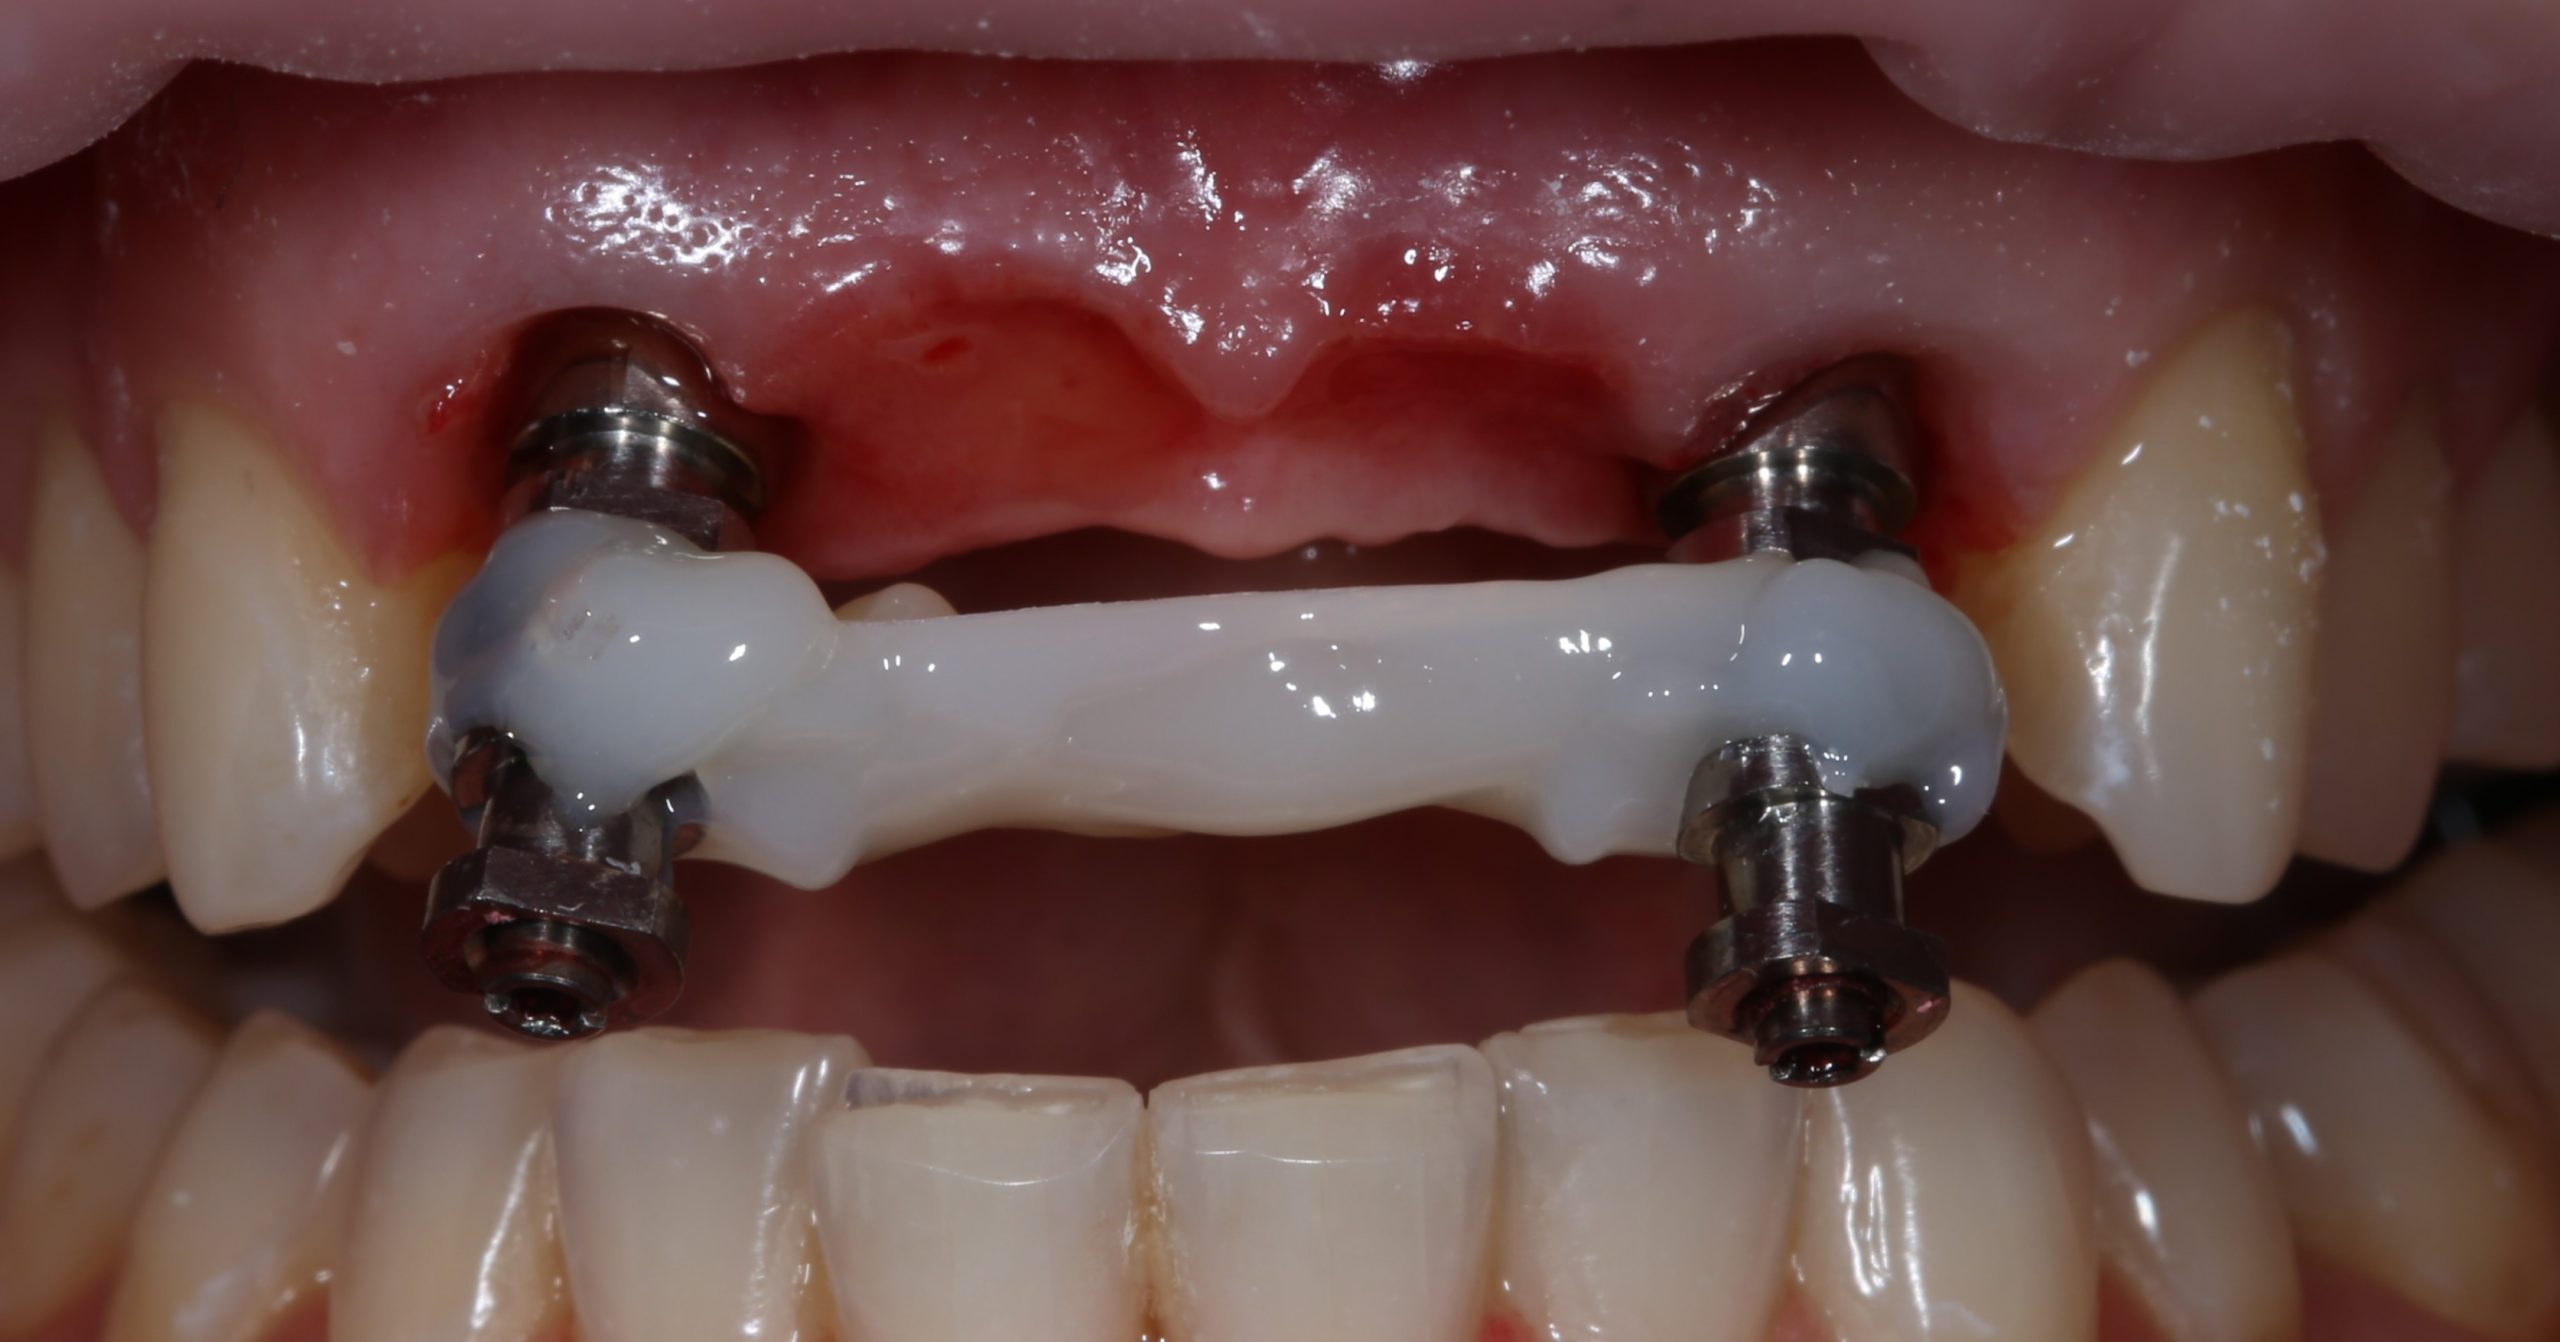

Фиксируем Esthetic Cap на имплантаты. Усилие при установке — 14 Нсм (больше ключ Xive не позволяет):

Еще раз проверим позиционирование имплантатов:

Поскольку трансгингивальная часть временного абатмента Esthetic Cap полностью перекрывает апертуру лунки зуба, мы можем обойтись без швов. Вообще без швов.

Теперь нужно сделать контрольные снимки, чтобы убедиться, что абатменты сели на платформу имплантата. В нашем случае, абатменты пришлось подточить:

Напомним, что еще до операции мы сделали временный протез с опорой на боковые резцы:

Всё, что нужно сейчас сделать Давиду — это приклеить почти готовый протез к абатментам. Что он и делает в течение 30-40 минут:

Как уже упоминалось выше, пересаженный соединительнотканный лоскут прижимается временными коронками центральных резцов, а потому не нуждается в дополнительной фиксации швами.

Итого, через полтора часа после удаления, фронтальная группа зубов Татьяны выглядит следующим образом: